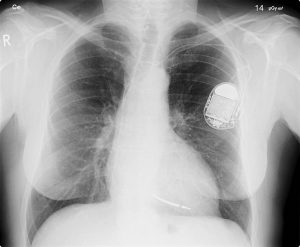

Just a few years ago, who would have thought that algorithms would be regularly making important decisions once made by humans, and they would be so complex that we would not be able to fully understand how they made their decisions (even though we rely on their decisions in life-threatening situations). And further, that algorithms would be operating within our bodies? I think this is just the beginning of the algorithmic revolution and we humans shouldn’t be surprised. This is because algorithms have actually been around for a very long time, we just didn’t recognize them. Essentially the evolution of life, is a full display of algorithms directing the actions of cells that make up our bodies. So, this means that below the level of consciousness there are trillions of algorithmic processes constantly occurring within our bodies. Thus far, the law hasn’t shown much interest in the algorithms operating within our bodies, with the exception of the question of whether algorithms are a process of nature and thus not patentable subject matter. But there are other legal issues impacted by the use of algorithms. For example, it is also the case that algorithms have been encroaching upon areas once thought solely to be within the domain of human creativity. On this point, algorithmic-based systems now write poems, news stories, and even novels. Algorithms, may also create paintings that reflect the style of the great Renaissance masters and they sometimes compose original music. If the issue is who owns the rights to such creative works (and that is an issue), it seems quite reasonable to conclude that the programmer owns the rights, or at least the owner of the software or computer providing the platform for the algorithm(s) which created the original works. But algorithms pose unique challenges to the law of intellectual property. For example, if an algorithm, learning on its own, creates a work of authorship, or invention, who is the owner? Under patent or copyright law, the owner cannot be a non-human entity, yet an algorithm operating autonomously from human input or control was the author or the inventor. This is not a neglected topic within law, but being actively discussed within the EU, US, Asia, and other jurisdictions. Moving on, what about the important topic of algorithms and fundamental rights, we all have rights, including constitutional and human rights. Considering our rights, it turns out that human biases have crept their way into the algorithms that make decisions which may affect people’s basic rights. So, for example, if an algorithm is trained with data that has inherent biases, then those biases may be expressed through an algorithm making decisions which affect humans. This is an important area of discussion within legal academia and an area where industry must be involved. Now, what about algorithms invading our bodies? By this I mean that algorithms which typically operated from the “outside” of the body are “migrating” to inside the body. How is this possible? Think for a moment about people with heart pacers, or cochlear or retinal implants, it turns out that algorithms are helping to control such systems, so clearly algorithms have breached the barrier between the outside external world and the inside internal world of the body. The heart pacer shown in the X-ray is an example.